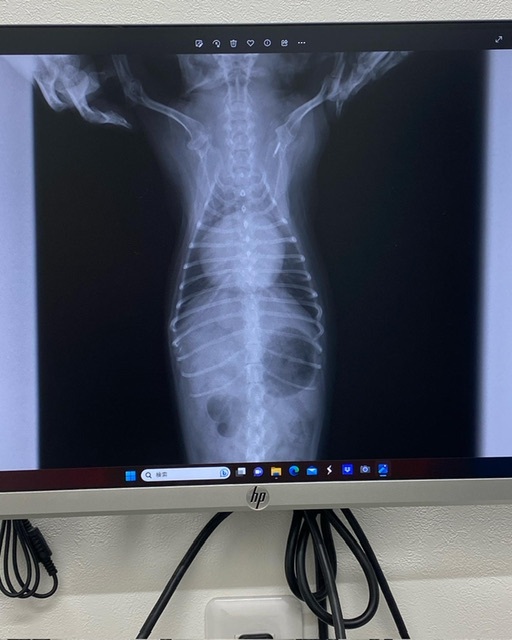

・胸部レントゲン

前回より少し大きくなっている

こんな小さな体で、こんなにも心臓が大きくなっちゃって…